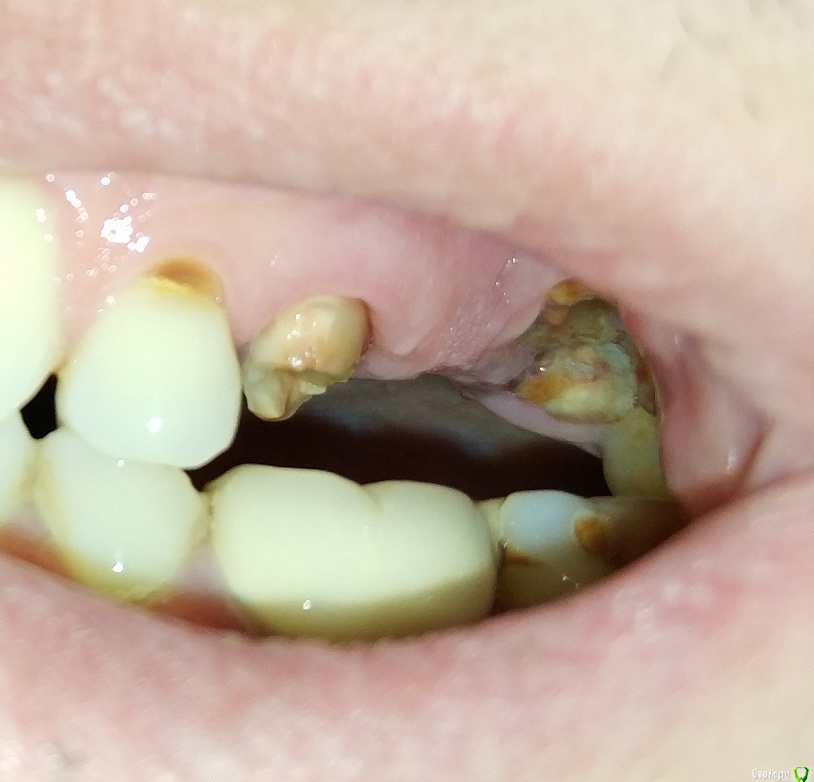

LTD Опубликовано 12 апреля, 2019 Поделиться Опубликовано 12 апреля, 2019 Мужчинка, 45 годов Слетел верхний мост 5-7 . Корень 7 (основание зуба ) отделился / разделился. «Целые» зубы 4, 8 не хочу трогать (обтачивать), решение зависит от бюджета. Просьба высказать мнение :а) Без имплантологии1 - делается ли вкладка на 7ку под дальнейший мост в таком состоянии? 2 - какие варианты восстановления возможны (съемные, бюгель и тд)?3 - какие варианты восстановления наиболее практичны по Вашему? б) хотя имплантация пока не по зубам Хочу понять:3 - на противоположной стороне 7-8 удачно стоит МК консоль на одном 7 зубе. Делается ли имплант с такой же конструкцией консоли на один 7-мой (который разрушен)?4 - делается ли одноэтапная имплантация на 7?5 - имеет ли смысл не удалять корни 7го с этой целью?6 - если 7 имплант + 567 мост (ставится ли мост - конструкция на 5й "свой") ?7 - возможность установки 7 без открытого лифта? Заранее спасибо! Ссылка на комментарий

krokomot Опубликовано 13 апреля, 2019 Поделиться Опубликовано 13 апреля, 2019 Вот могут же пациенты, себя хорошо сфотографировать, что всё видно и понятно, присоединяюсь к коллегам, но нижний зуб под коронкой тоже от жил свое... 2 Ссылка на комментарий